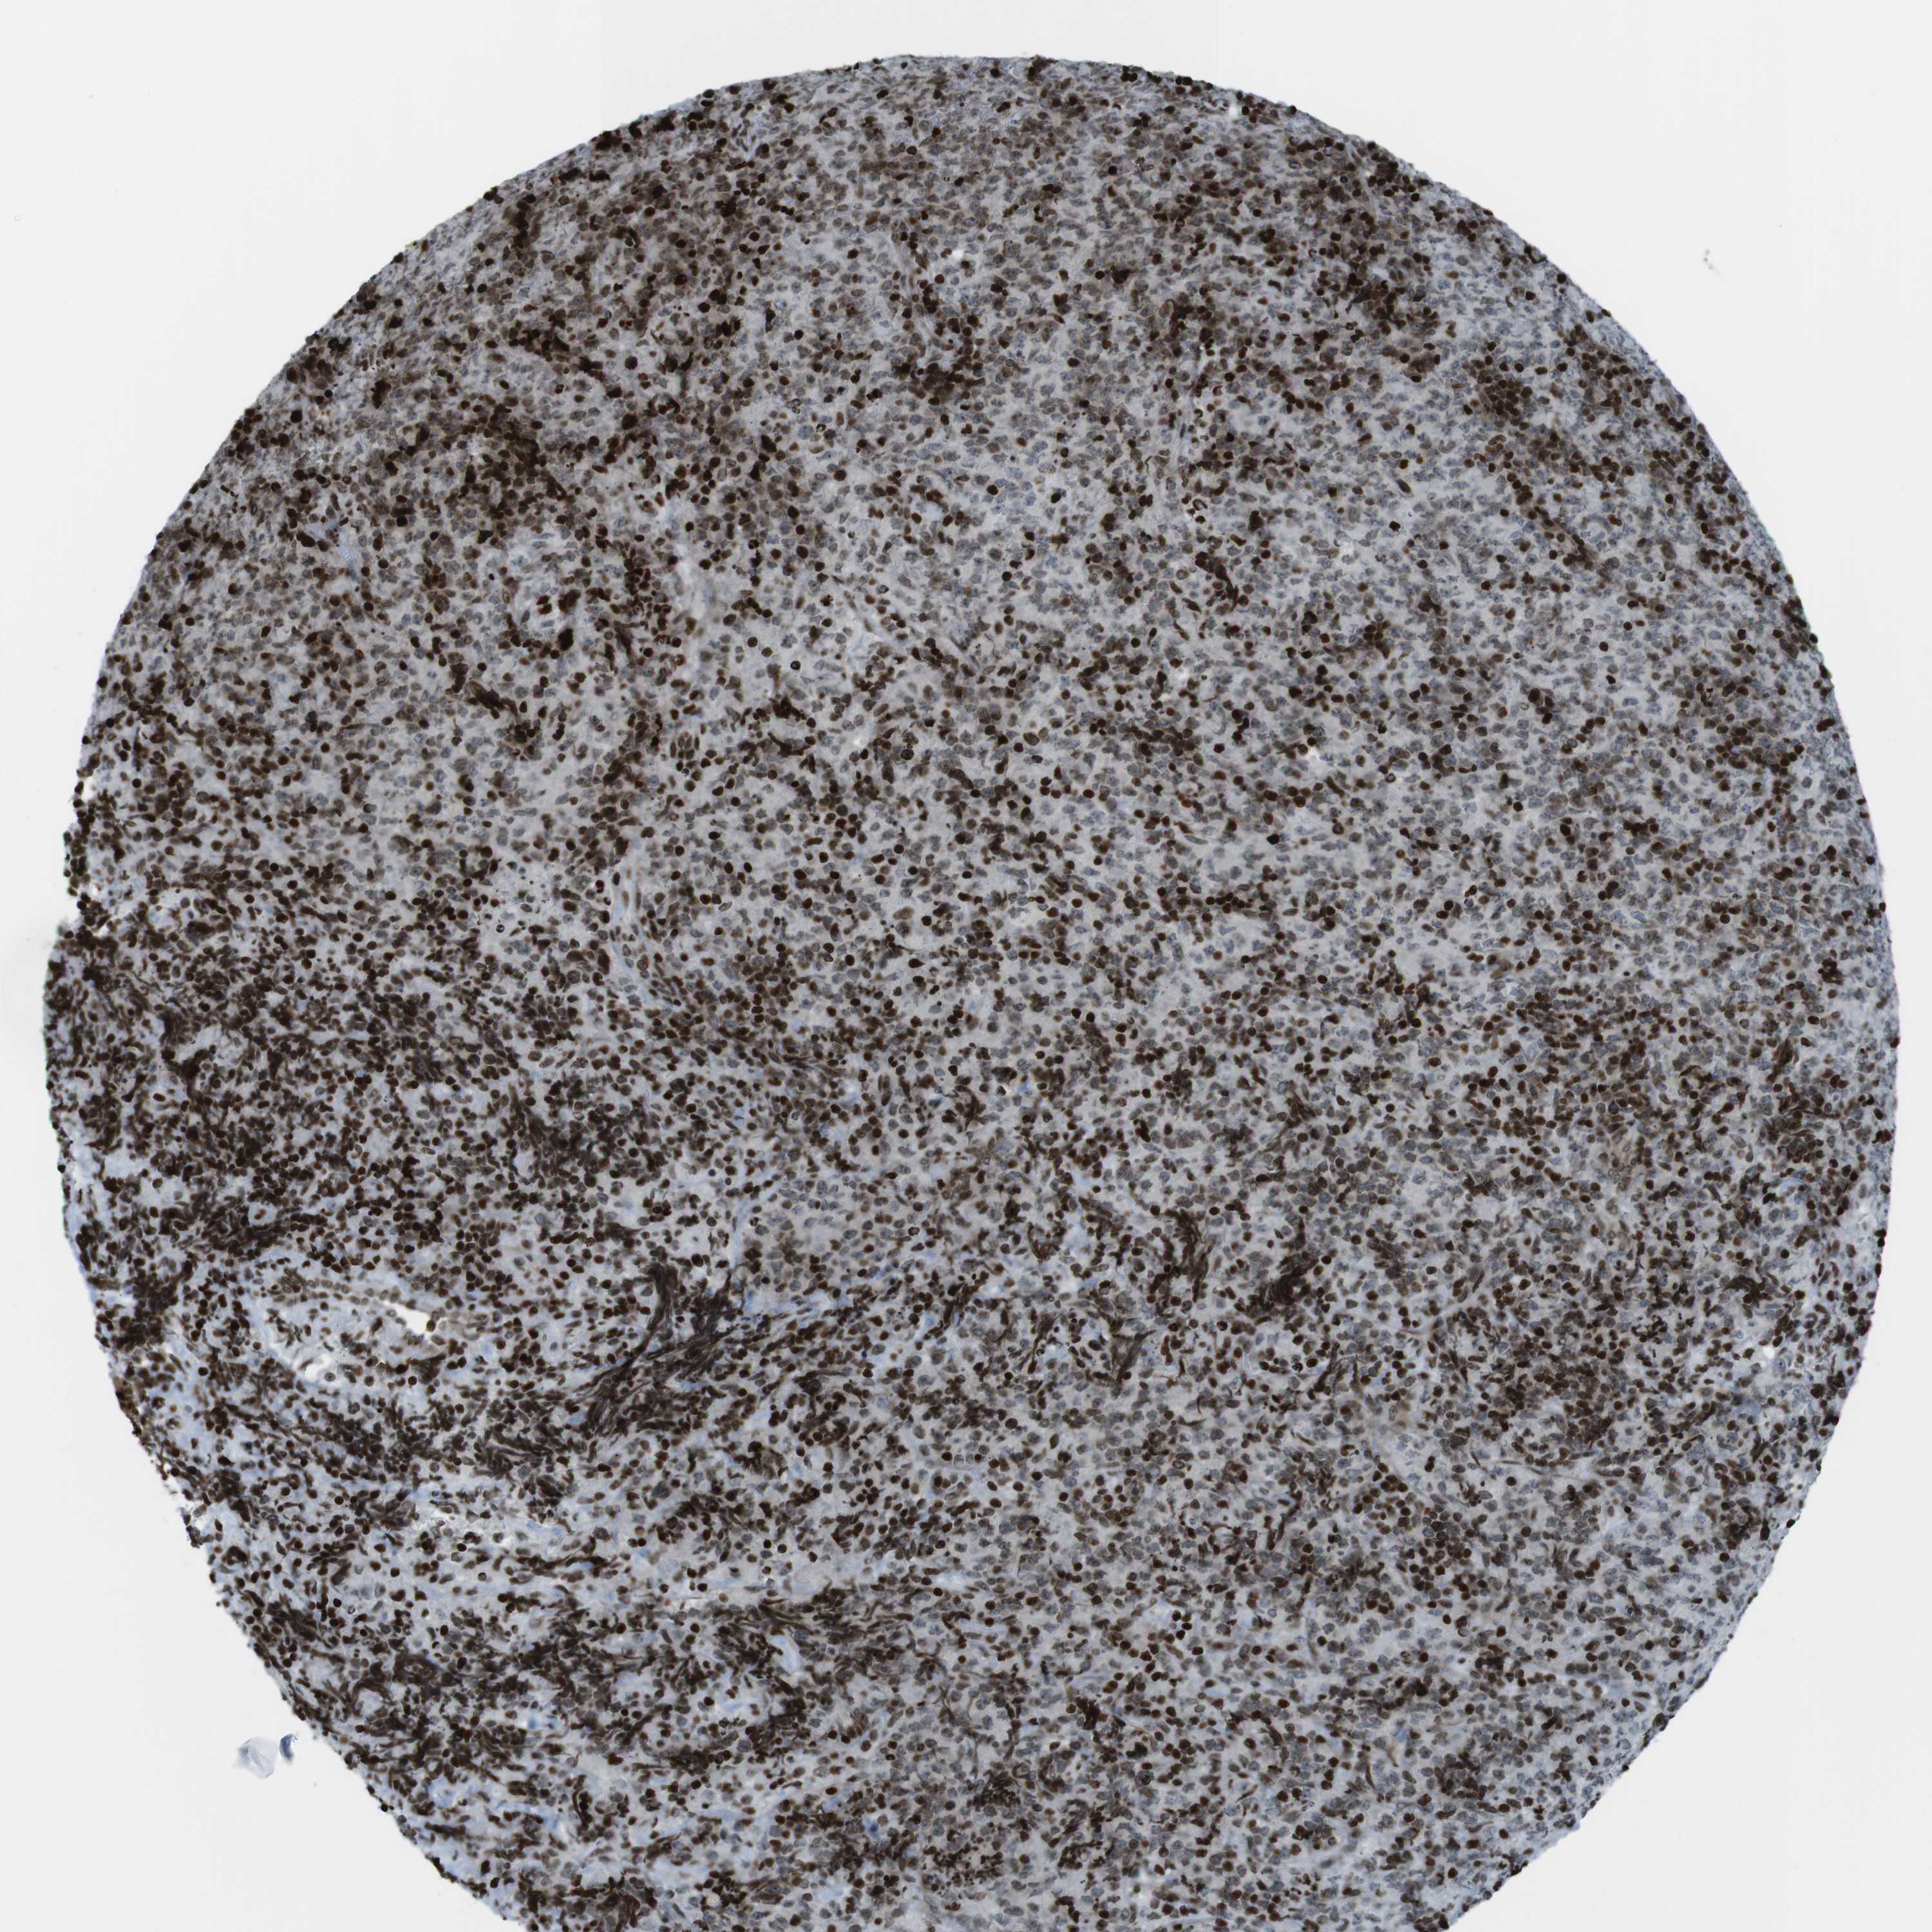

CANCER LYMPHOMA Show tissue menu

Lymphoma

LYMPHOMA - Protein expressioni

A mouse-over function shows sample information and annotation data. Click on an image to view it in a full screen mode. Samples can be filtered based on level of antibody staining by selecting one or several of the following categories: high, medium, low and not detected. The assay and annotation is described here.

Antibody stainingi

Antibody staining in the annotated cell types in the current human tissue is reported as not detected, low, medium, or high, based on conventional immunohistochemistry profiling in selected tissues. This score is based on the combination of the staining intensity and fraction of stained cells.

Each image is clickable and will lead to virtual microscopy that enables deeper exploration of all samples and also displays staining intensity scores, fraction scores and subcellular localization as well as patient and tissue information for each sample.

Antibody HPA041189

Antibody CAB012242

Staining

High

Medium

Low

Not detected

Intensity

Strong

Moderate

Weak

Negative

Quantity

>75%

75%-25%

<25%

None

Location

Nuclear

Cytoplasmic/membranous

Cytoplasmic/membranous,nuclear

Hodgkin's disease, NOS

Malignant lymphoma, non-Hodgkin's type, High grade

Malignant lymphoma, non-Hodgkin's type, Low grade